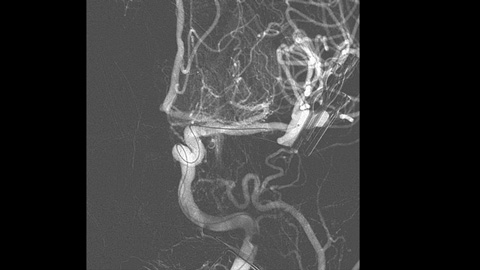

Klinische Anwender verlassen sich auf die klassische DSA-Bildgebung als wichtigste Informationsquelle während des gesamten Eingriffs.

Fall mit freundlicher Genehmigung von Dr. Vitor Mendes Pereira, UHN, University of Toronto, Toronto, Kanada

Patient:

19. Juli 2012

13. Oktober 2014